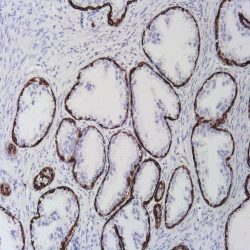

| Dilution | 1:50 |

| Staining | Cytoplasm |

| Control tissue | Tissue section from chromophobe carcinoma of the kidney |